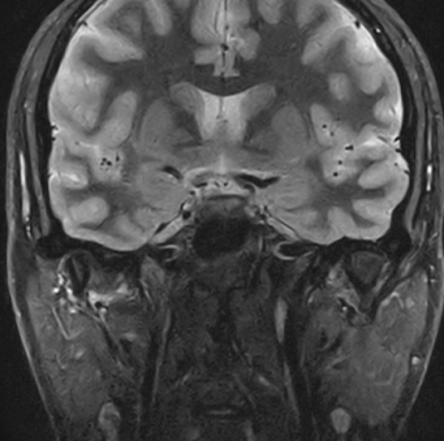

非浸潤性乳管癌 Ductal Carcinoma In Situ(DCIS)